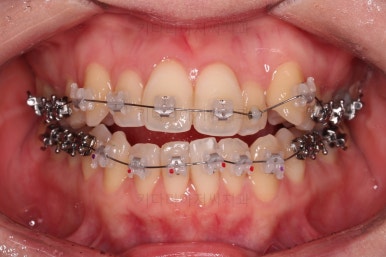

초진 시, 입안의 모습입니다.

좌측 송곳니가 덧니처럼 튀어나가 있고, 송곳니 옆의 작은 억므니가 안으로 쏙 들어가서 덧니 느낌이 더 강조되어 보이네요.

위아래 앞니가 긴밀하게 겹침이 없는 약간의 개방교합(오픈바이트, Openbite) 경향이 보입니다.

웃거나 말할 때 드러나는 치열이 삐뚤어서 심미적으로 좋지 못하고요.

철사가 들어가니 삐뚤한 치열이 더 강조되어 보이네요.